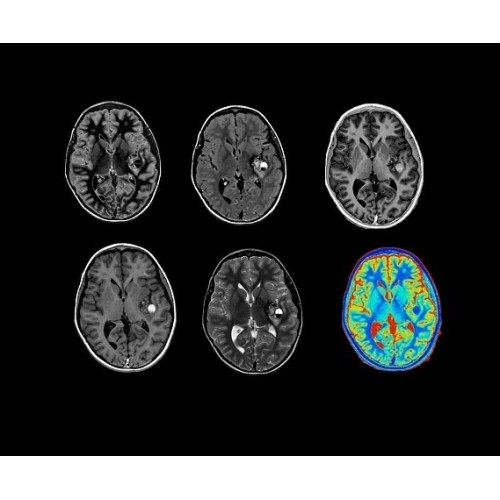

SIGNA PET/MR 3.0T — это гибридная система, в которой совмещаются две принципиально разные технологии — магнитно-резонансную томографию (МРТ) и позитронно-эмиссионную томографию (ПЭТ). Система отличающийся высокой чувствительностью и эффективностью и предназначена для диагностики в области онкологии, неврологии, кардио-васкулярных исследований, исследований воспалительных процессов.

Компания GE Healthcare представляет революционную, полностью интегрированную систему SIGNA PET/MR1, в которой сочетаются времяпролетная технология (TOF) и возможности напряженности магнитного поля 3.0 Тл. Мы поможем вам поднять исследования на более высокий уровень. SIGNA PET/MR позволяет достичь впечатляющей точности и скорости исследований, а благодаря новейшей технологии реконструкции Q.Clear2 качество изображений улучшается в два раза. Кроме того, в систему включен полный набор клинических приложений и гибких катушек для проведения любых видов исследования, открывая для вас возможности визуализации, о которых вы даже не догадывались.

Кроме того, в результате использования технологии TOF и инновационной технологии реконструкции Q.Clear вы сможете добиться прекрасного соотношения сигнал/шум. А благодаря технологии нулевого времени эхо (ZTE) визуализировать костную структуру без ионизирующего излучения. Все эти разработки для улучшения качества сканирования и точности анализа помогут вам использовать весь потенциал ПЭТ/МРТ.

• Q.Clear — в основу технологии легли накопленные знания о том, как минимизировать помехи при реконструкции и получить четкое изображение. При значительном улучшении качества изображения сохраняется точность расчетов. Сочетание технологии TOF и реконструкции Q.Clear — ваш надежный помощник для получения точных и достоверных данных.

• МРТ с функцией нулевого времени эхо (ZTE) отличается точностью, возможностью персональных настроек и отсутствием ионизирующего излучения. Она приходит на смену традиционному исследованию на основе рентгеновского излучения. МРТ с функцией нулевого времени эхо (ZTE) на базе SIGNA ПЭТ/МРТ является более надежной и быстрой по сравнению с системами, использующими сверхмалое время эхо (UTE).

• Специальный пакет приложений для измерения и сравнения объемных изображений ЦНС с нормами поможет вам в диагностике нейродегенеративных заболеваний, а дополнительные инструменты визуализации — в постановке точного диагноза с помощью бета-амилоидов и радиоизотопных маркеров ФДГ.